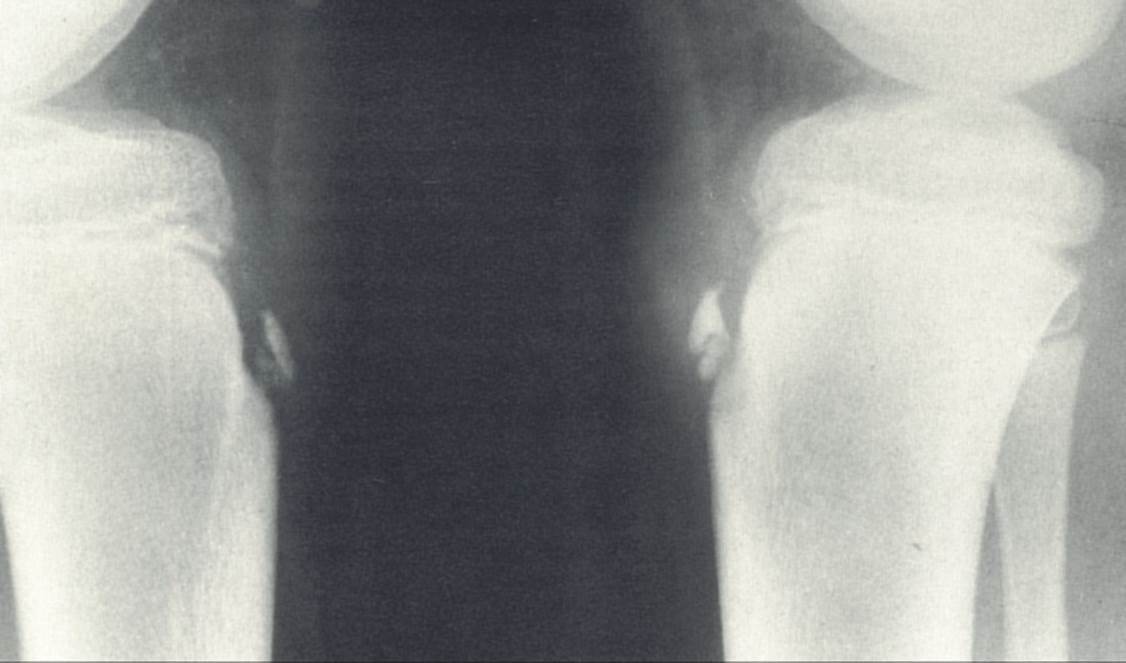

Legg-calve-perthes disease

Kohler’s disease**

Kohlers disease radiographic findings

(right is sclerotic)